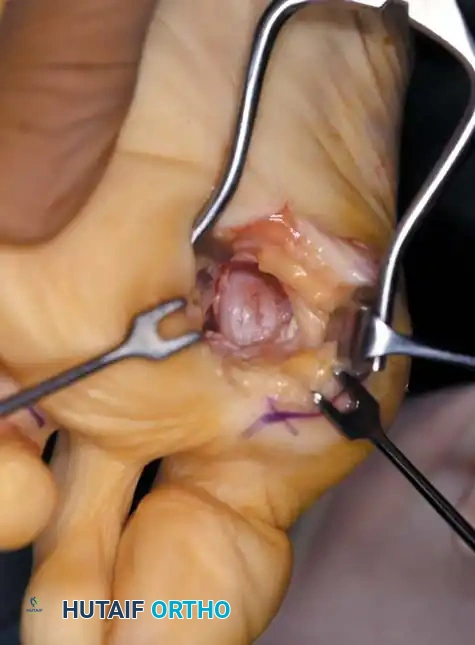

• Using a Freer elevator or a small osteotome for its strength, mobilize the fi bular sesamoid (Fig. 78-31A to C). This may be diffi cult in elderly patients with signifi cant deformity and adherence of the sesamoid to the metatarsal head. Lift the metatarsal dorsally for exposure (Fig. 78-31D and E).

Fig. 78-31 Excision of fi bular sesamoid in modifi ed Keller procedure. With base of proximal phalanx removed and medial eminence excision, exposure of fi bular sesamoid is not as diffi cult from medial incision. A, Operative photograph showing elevation of fi rst metatarsal with strong two-tooth retractor and use of small osteotome to mobilize fi bular sesamoid and lateral capsuloligamentous (frequently contracted) structures. Osteotome is between metatarsal head and lateral sesamoid. When mobilization of fi bular sesamoid is complete, entire sesamoid is visible for excision. Note chondromalacia of tibial sesamoid articular surface medial to osteotome. B, Fibular sesamoid has been excised, and lateral capsular structures and conjoined tendon (in forceps) have been released. Neurovascular bundle to lateral side of hallux is adjacent to these structures. C, Diagrammatic representation of modifi ed Keller procedure. By excising fi bular sesamoid, valgus moment of conjoined tendon of fl exor hallucis brevis and adductor hallucis no longer pulls fl exor hallucis longus tendon laterally (carrying hallux with it) through capsulosesamoid plantar plate and pulley system. D, Metatarsal head must be lifted dorsally to excise fi bular sesamoid under direct vision. E, Note exposure of fi bular sesamoid after mobilization of metatarsal head. Continued